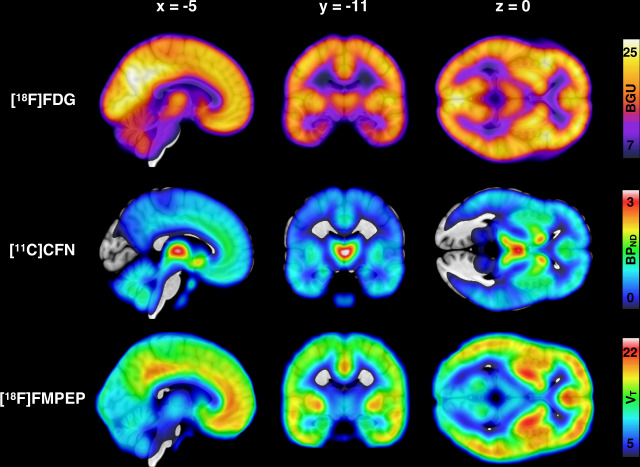

Mean distribution of BGU, MOR availability and CB1R availability are shown in Fig. 1. Descriptive Pearson correlations of the sample are presented in the Supplementary Fig. 1 and Supplementary Table 2.